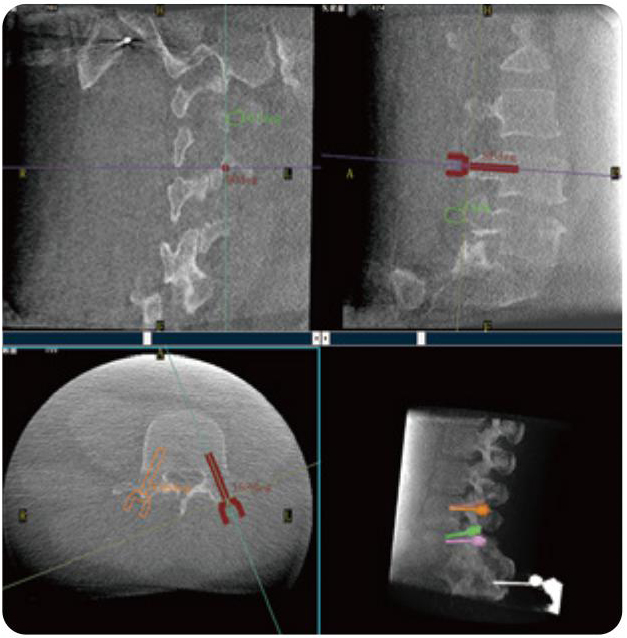

PL300B可應用于多節(jié)段脊柱外科手術,輔助醫(yī)生定位病灶部位,為脊柱外科手術(經(jīng)皮椎體成形術、椎弓根螺釘內(nèi)固定術等術式)提供術前手術流程規(guī)劃、入釘位置、角度可視化引導,模擬仿真入釘輔助。

PL300B搭配普愛醫(yī)療自主研發(fā)生產(chǎn)的平板3D C形臂,借助一體化自適應配準( 軌跡配準)技術,通過追蹤C形臂三維采集軌跡,自動完成圖像坐標建立和系統(tǒng)坐標配準。配準精度更高,操作步驟少,系統(tǒng)運作效率高。